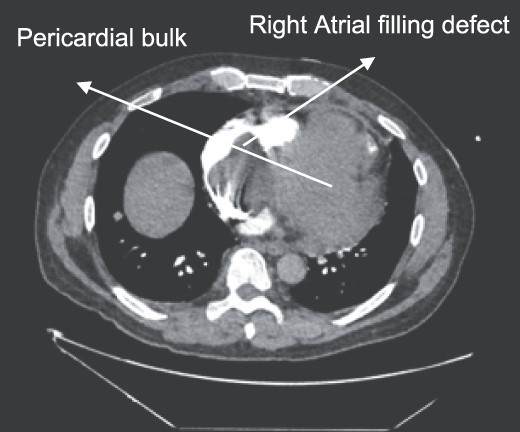

A 52-year-old gentleman was admitted to a district general hospital for shortness of breath causing type 1 respiratory failure with oxygen saturations of <90% despite high flow oxygen. His past medical history was unremarkable, and he was usually fit and well. A CT Pulmonary Angiogram (CTPA) was undertaken, which showed a heterogeneous oval-shaped lesion measuring 15 × 9 × 14 cm3 between the heart and the diaphragm, with a median attenuation of 35 HU and no enhancement during the arterial phase. Further solid lesions of 14 mm in the right lower lobe and 5 mm in the right upper lobe raised the suspicion of a primary cardiac sarcoma with pulmonary metastasis. This is shown in Fig. 1. Subsequent urgent CT staging (Fig. 2) was undertaken, which confirmed an indeterminate space occupying the inferior pericardial space, right atrial (RA) filling defect and anterior nodular pericardial thickening. No intra-abdominal or bone lesions were identified. An echocardiogram also confirmed these finding with the addition of no flow through the tricuspid valve (TV), as shown in Fig. 3.

CTPA showing oval-shaped heterogenous lesion as well as RA filling defect.